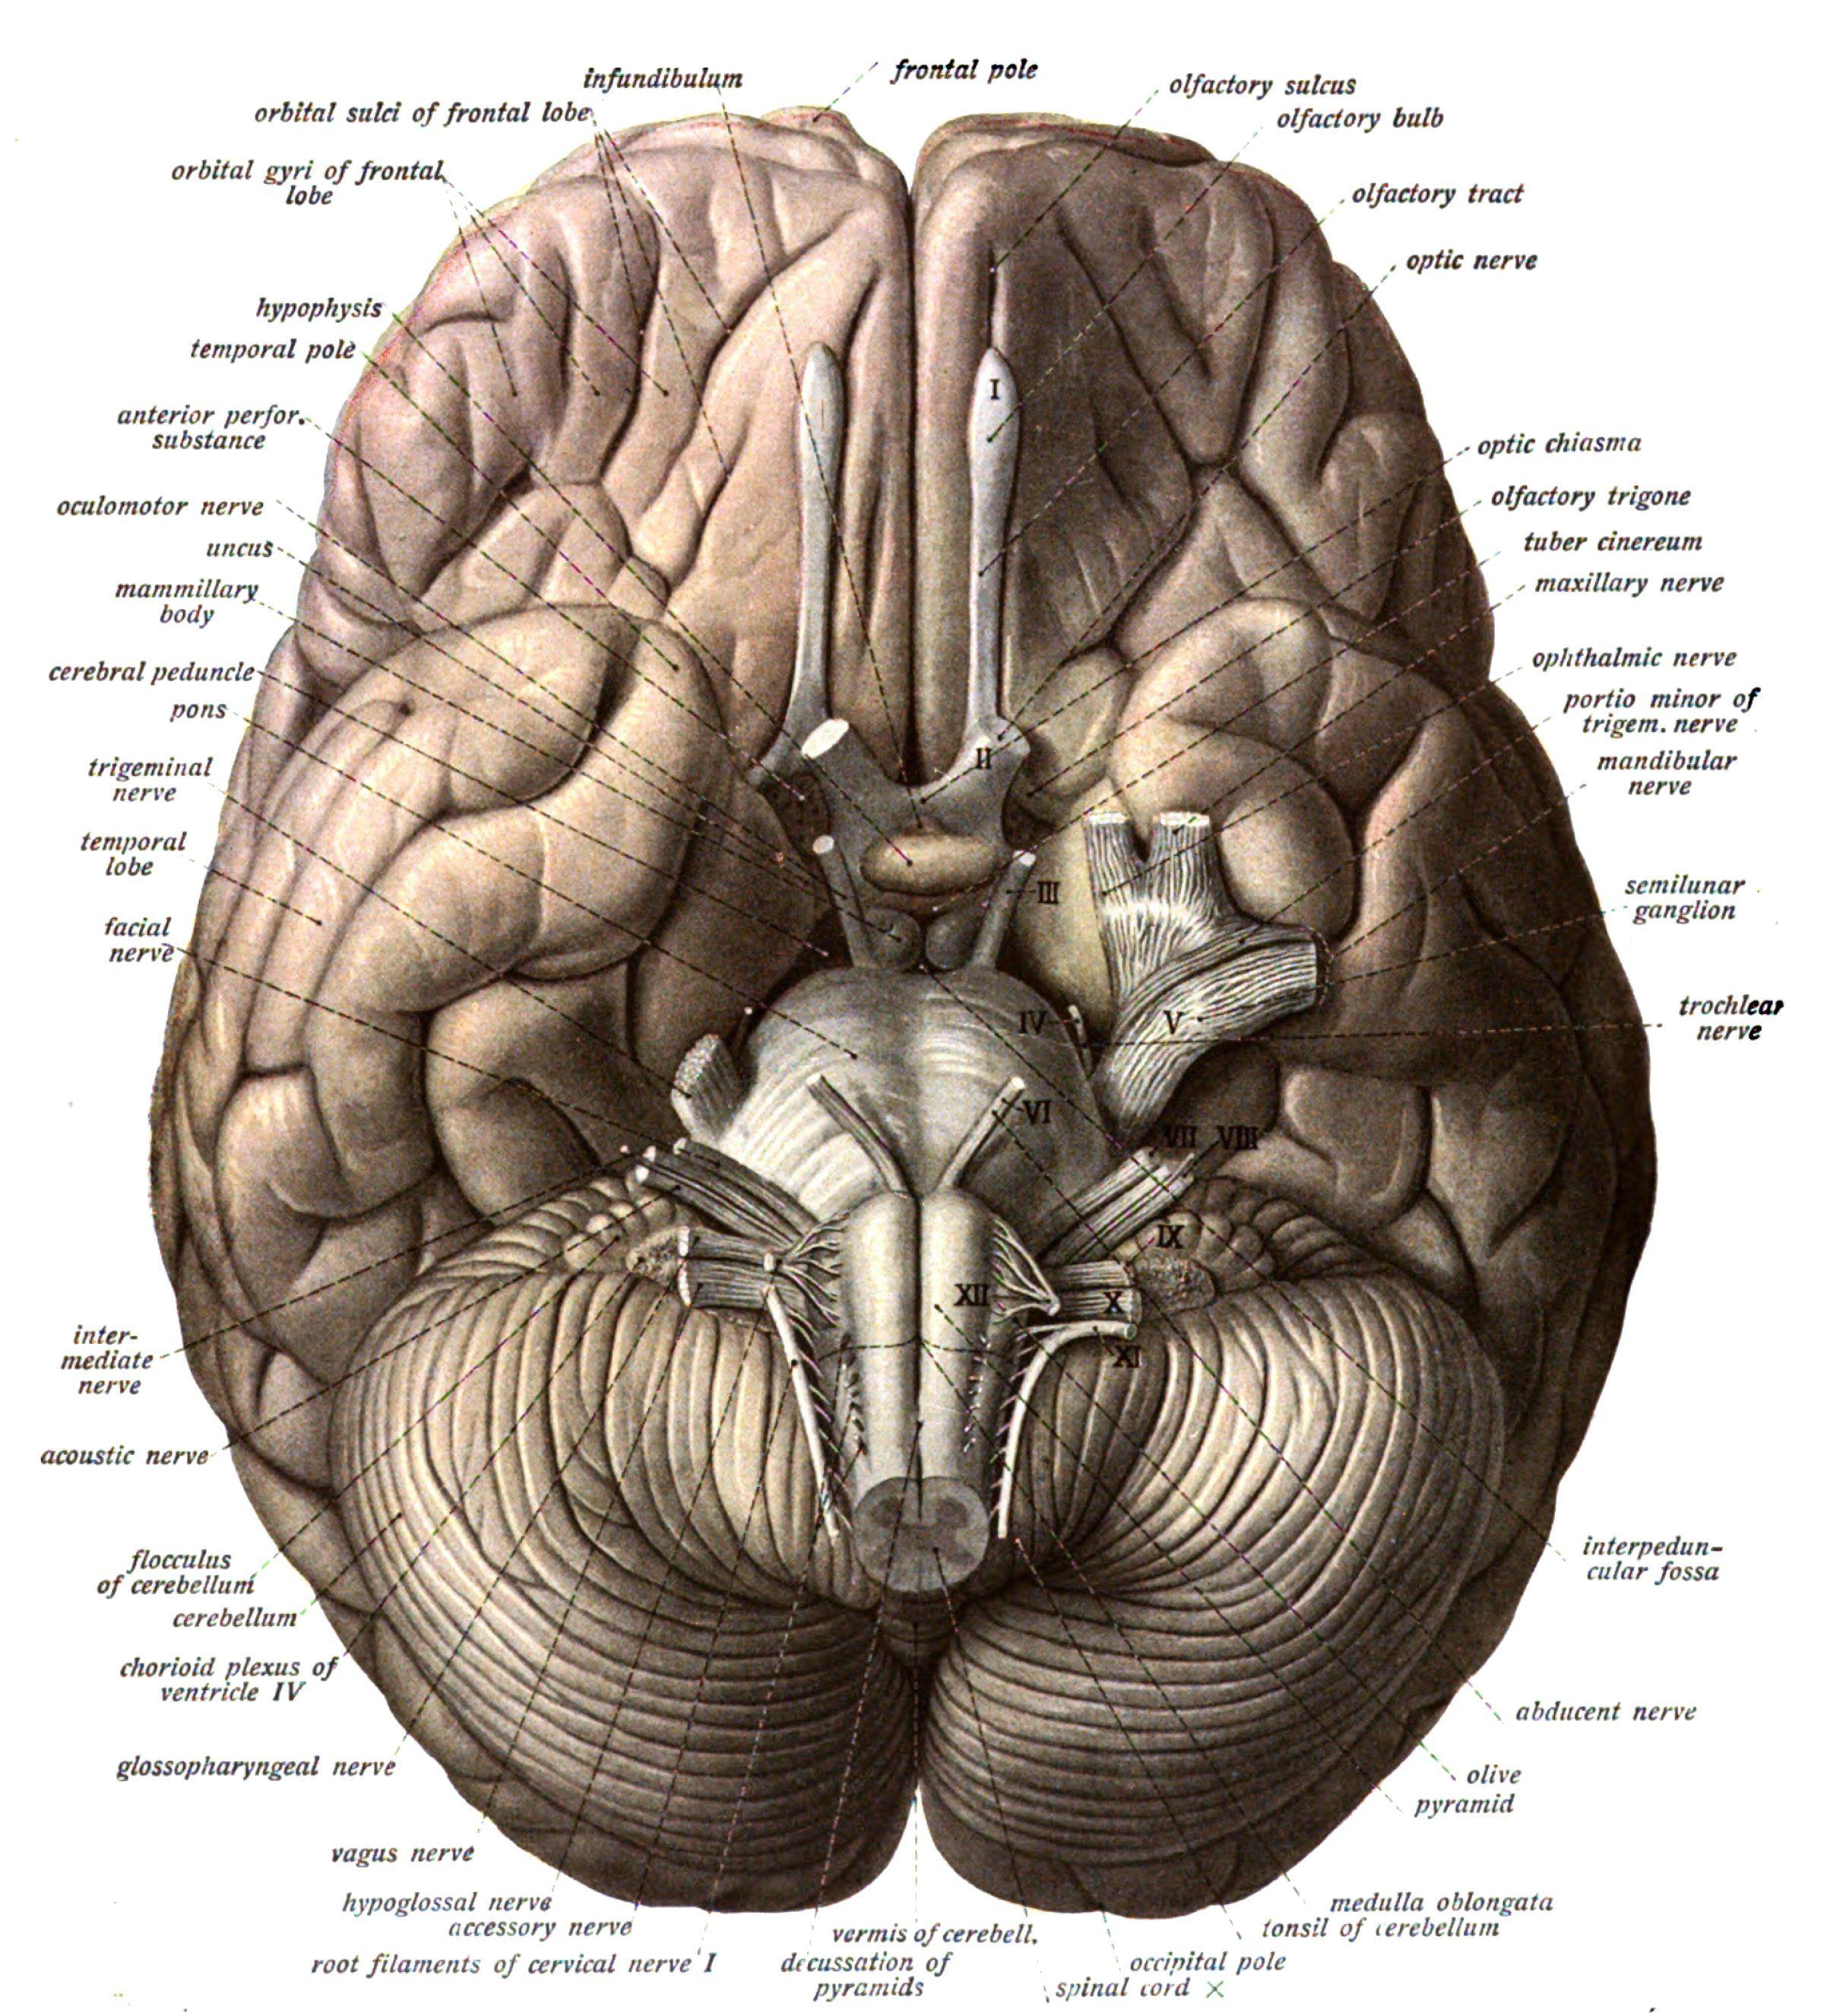

Brain Anatomy Wallpapers - Top Free Brain Anatomy Backgrounds

wallpaperaccess.combegins wallpaperbat wallpapersafari

wallpaperaccess.combegins wallpaperbat wallpapersafari